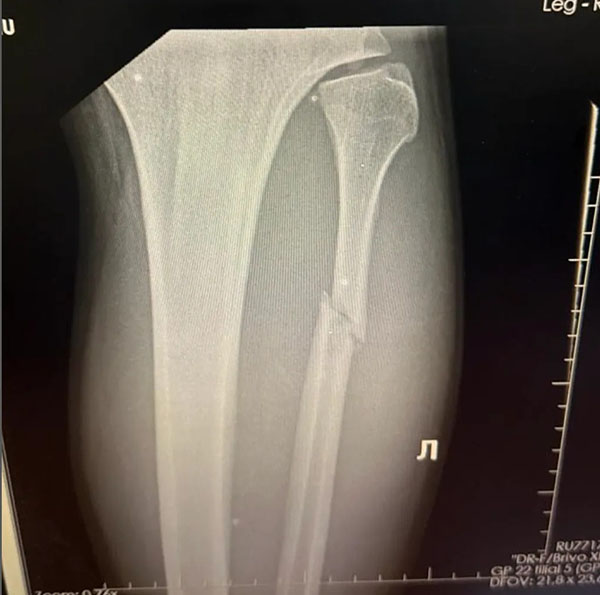

«Όλοι νόμιζαν ότι υπερβάλλω, γιατί περπατούσα, κουτσαίνοντας μεν, αλλά περπατούσα. Όταν όμως πήγα για ακτινογραφία, ο γιατρός μου έδειξε ότι η περόνη ήταν σπασμένη στα δύο.»

Ευτυχώς, ο Walker δεν χρειάζεται χειρουργείο. Ο γιατρός του επιβεβαίωσε ότι το κάταγμα δεν είναι πλήρες, και του συνέστησε ακινητοποίηση με γύψο για 5–6 εβδομάδες, χωρίς να πατάει καθόλου το πόδι.